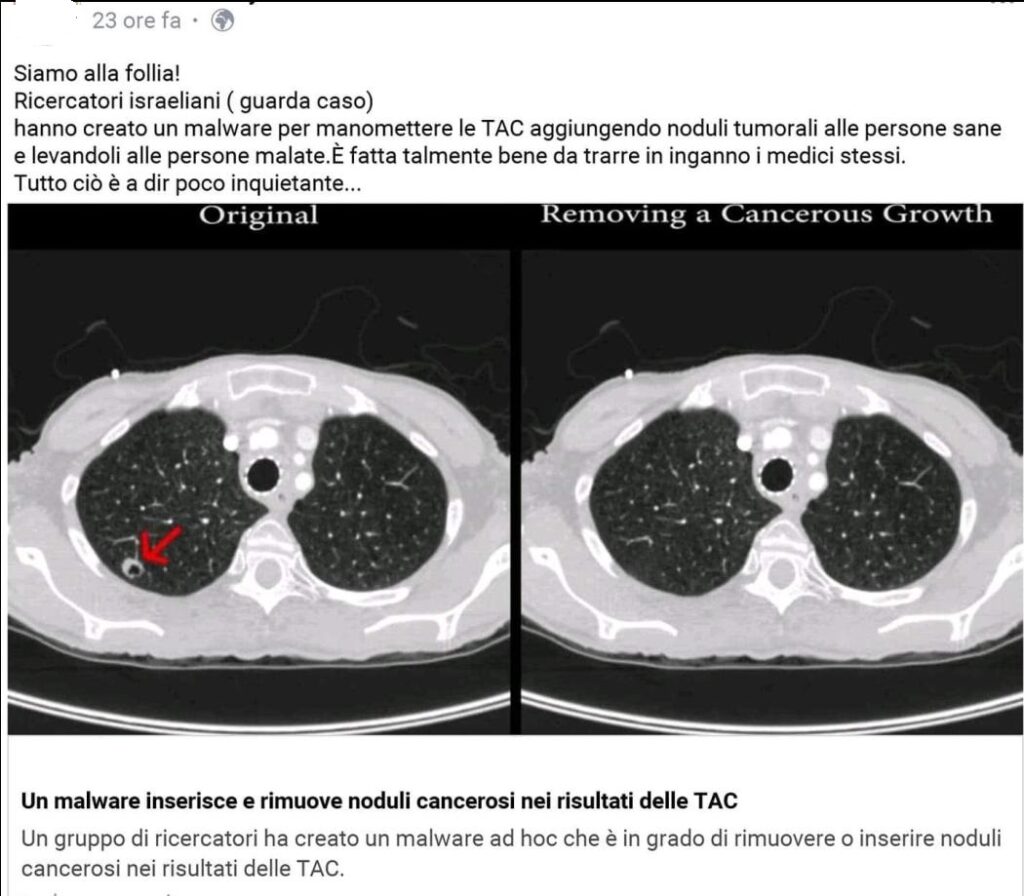

«Hanno creato un malware per manomettere le TAC aggiungendo noduli alle persone sane e levandoli alle persone malate»

KF gestisce un profilo Facebook cospirativista dedicato ad una martellante campagna di diffusione di grossolane teorie antiscientiste, in modo particolare vengono lanciati strali contro le vaccinazioni viste come un’azione pianificata a livello globale da fantomatici sionisti-massoni allo scopo di uccidere (vittime principali gli infanti) e schiavizzare tutti quelli che si oppongono alla presa di “potere sionista“, al vertice di questo “sistema sionista massonico” ci sarebbero la famiglia Rothschild e George Soros. Il tono predicatorio aduso agli slogan semplicistici e zuccherosi usato da KF ed i suoi numerosi followers, nasconde però un’aggressività di fondo che si esplicita in inviti ad uccidere i medici vaccinisti (“Vanno catturati i medici ed uccisi. Assolutamente!”) e colpire gli “Illuminati” e “Massoni-Sionisti” che si anniderebbero dietro le varie cospirazioni globali. In uno dei suoi numerosi post antiscientisti, KF accusa medici israeliani di avere creato un malware allo scopo di far risultare malate di tumore le persone sane. Oltre alla propaganda cosiddetta “No-Vax” KF condivide tutte le maggiori teorie della cospirazione, tra cui quella del “complotto globale”, ovvero misteriosi quanto fantomatici “Illuminati” sarebbero all’opera su un “piano subdolo” che: «comincia dal finto riscaldamento globale passando per le nanotecnologie fino ad arrivare al controllo totale, non solo del clima ma di tutti gli esseri umani. Ci sono milioni di persone coinvolte e farle tacere tutte, facendo parlare compiacevoli media di regime dovrebbe farvi capire l’enormità del complotto e la nostra impotenza.»